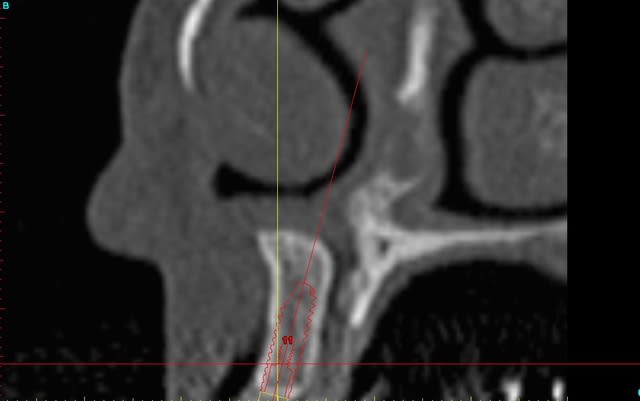

le scan n'est pas terrible, mais suffisant pour voir que 22 une fois extraite, ne va pas etre simple à implanter, par contre 11/21 avec un peu d'expansion...

Des lecross section21 jinha0 - Eugenol

Des lecross section sf6tbl - Eugenol

Des le cross section 12 vyz5ug - Eugenol

Des le cross section 22 w31w6b - Eugenol